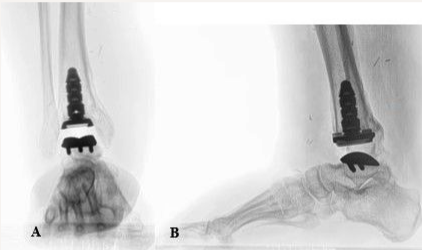

The procedures performed included right TAA, posterior tibiotalar joint capsulotomy, talonavicular joint capsulotomy, Achilles tendon lengthening, the intertarsal synovectomy of the midtarsal joint, and tibia reinforcement (Figure 3). The latissimus dorsi muscle was isolated and anastomosed to the posterior tibial artery during the subsequent plastic surgery procedure.